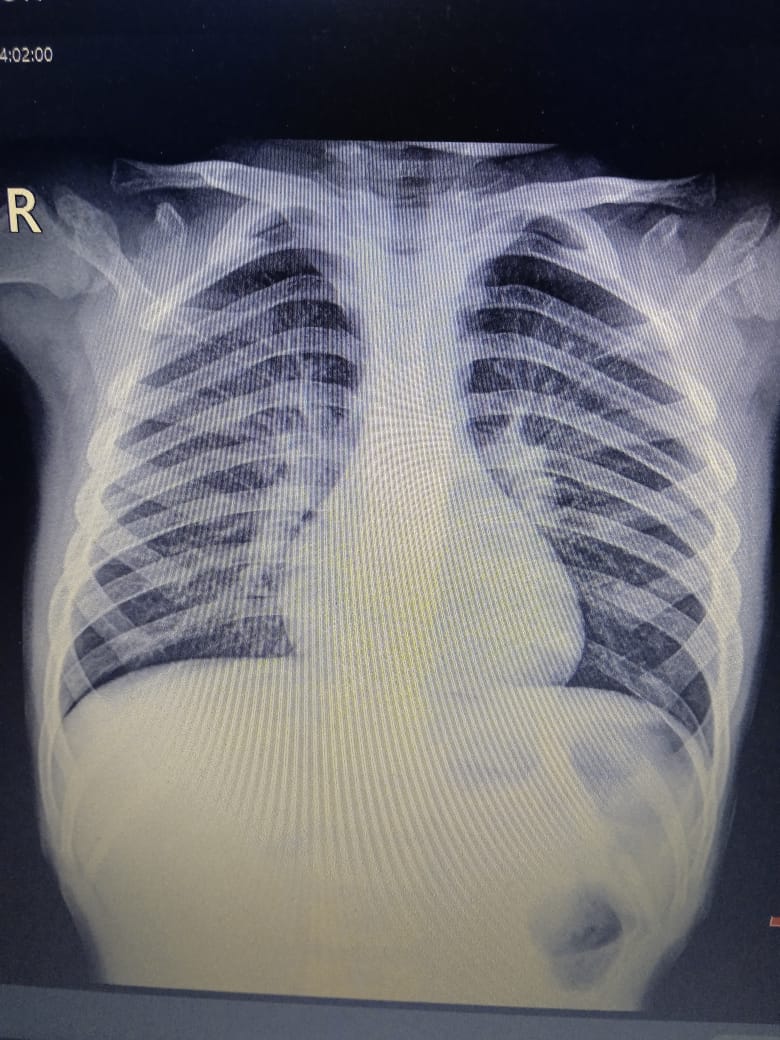

Su consejo fue una orden llena de esperanza: Vaya al hospital mañana, repita los exámenes y búsqueme. Les haremos placas de tórax. Esa intervención no fue casual; fue el cable a tierra que necesitaba para no desconectarme por completo.

Era la confirmación de que, incluso en la soledad más absoluta, la bondad humana puede aparecer en las formas más insospechadas. Los resultados definitivos de algunos exámenes tardarán, pero por ahora tenemos un diagnóstico claro y un tratamiento que seguir. La neumonía bilateral en mis dos niños pequeños y la bronquitis en mi hijo mayor son condiciones serias, pero por fin tienen un nombre y un camino a seguir.

Her advice was a hopeful command: Go to the hospital tomorrow, repeat the tests, and find me. We'll take chest X-rays. That intervention wasn't a coincidence; it was the anchor I needed to keep from completely disconnecting.

The final results of some tests will take time, but for now we have a clear diagnosis and a treatment plan. Bilateral pneumonia in my two young children and bronchitis in my older son are serious conditions, but they finally have a name and a path forward.